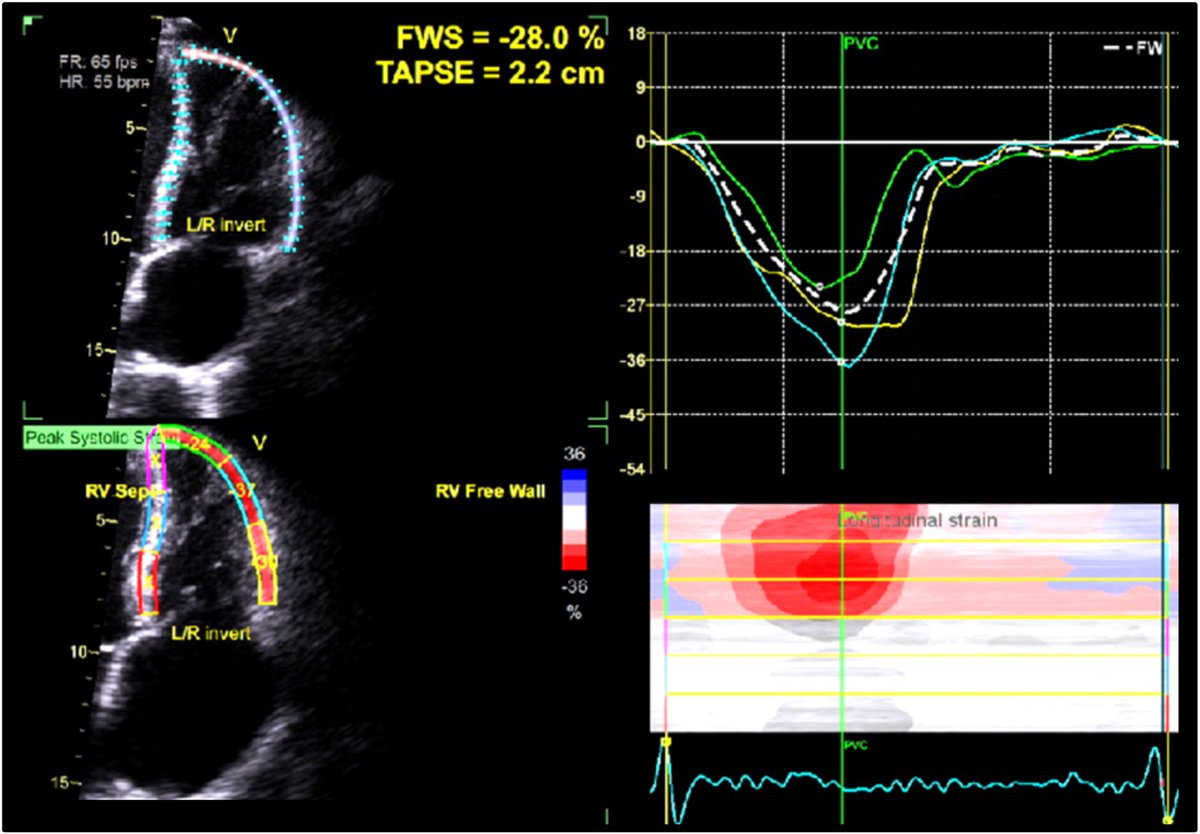

🫀NEW GUIDELINE🫀 Read our newest #ASEGuideline, "Clinical Applications of Strain Echocardiography," developed in collaboration with the European Association of Cardiovascular Imaging of the @escardio! https://t.co/cbZg6KbbX0